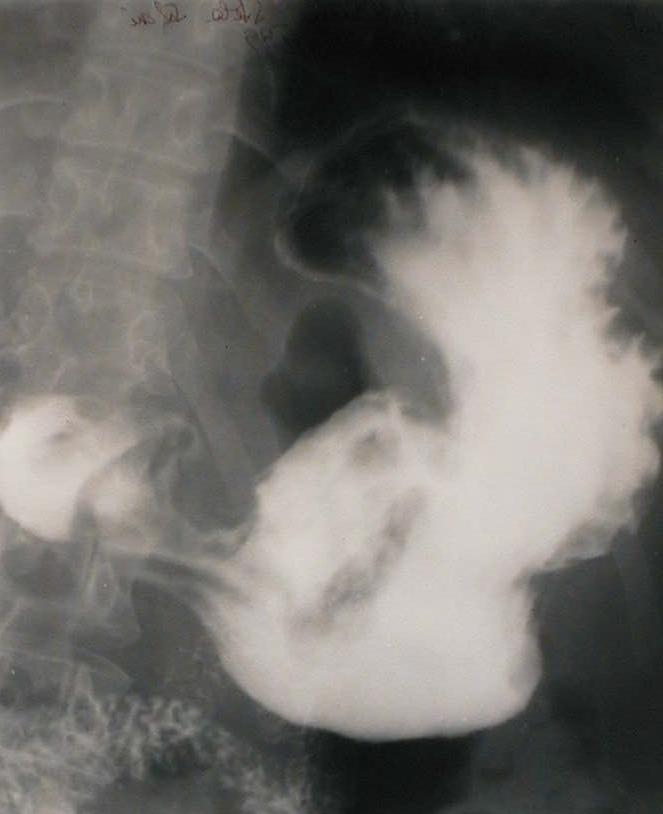

Barium Contrast Radiography: large crater which erodes into a mass( filling-defect) on the lesser curve, below the gastric angle.

Tranzit baritat: nișă gigantă încastrată într-o lacună a micii curburi, sub unghiul gastric. Ancoșă pe marea curbură, în dreptul nișei.